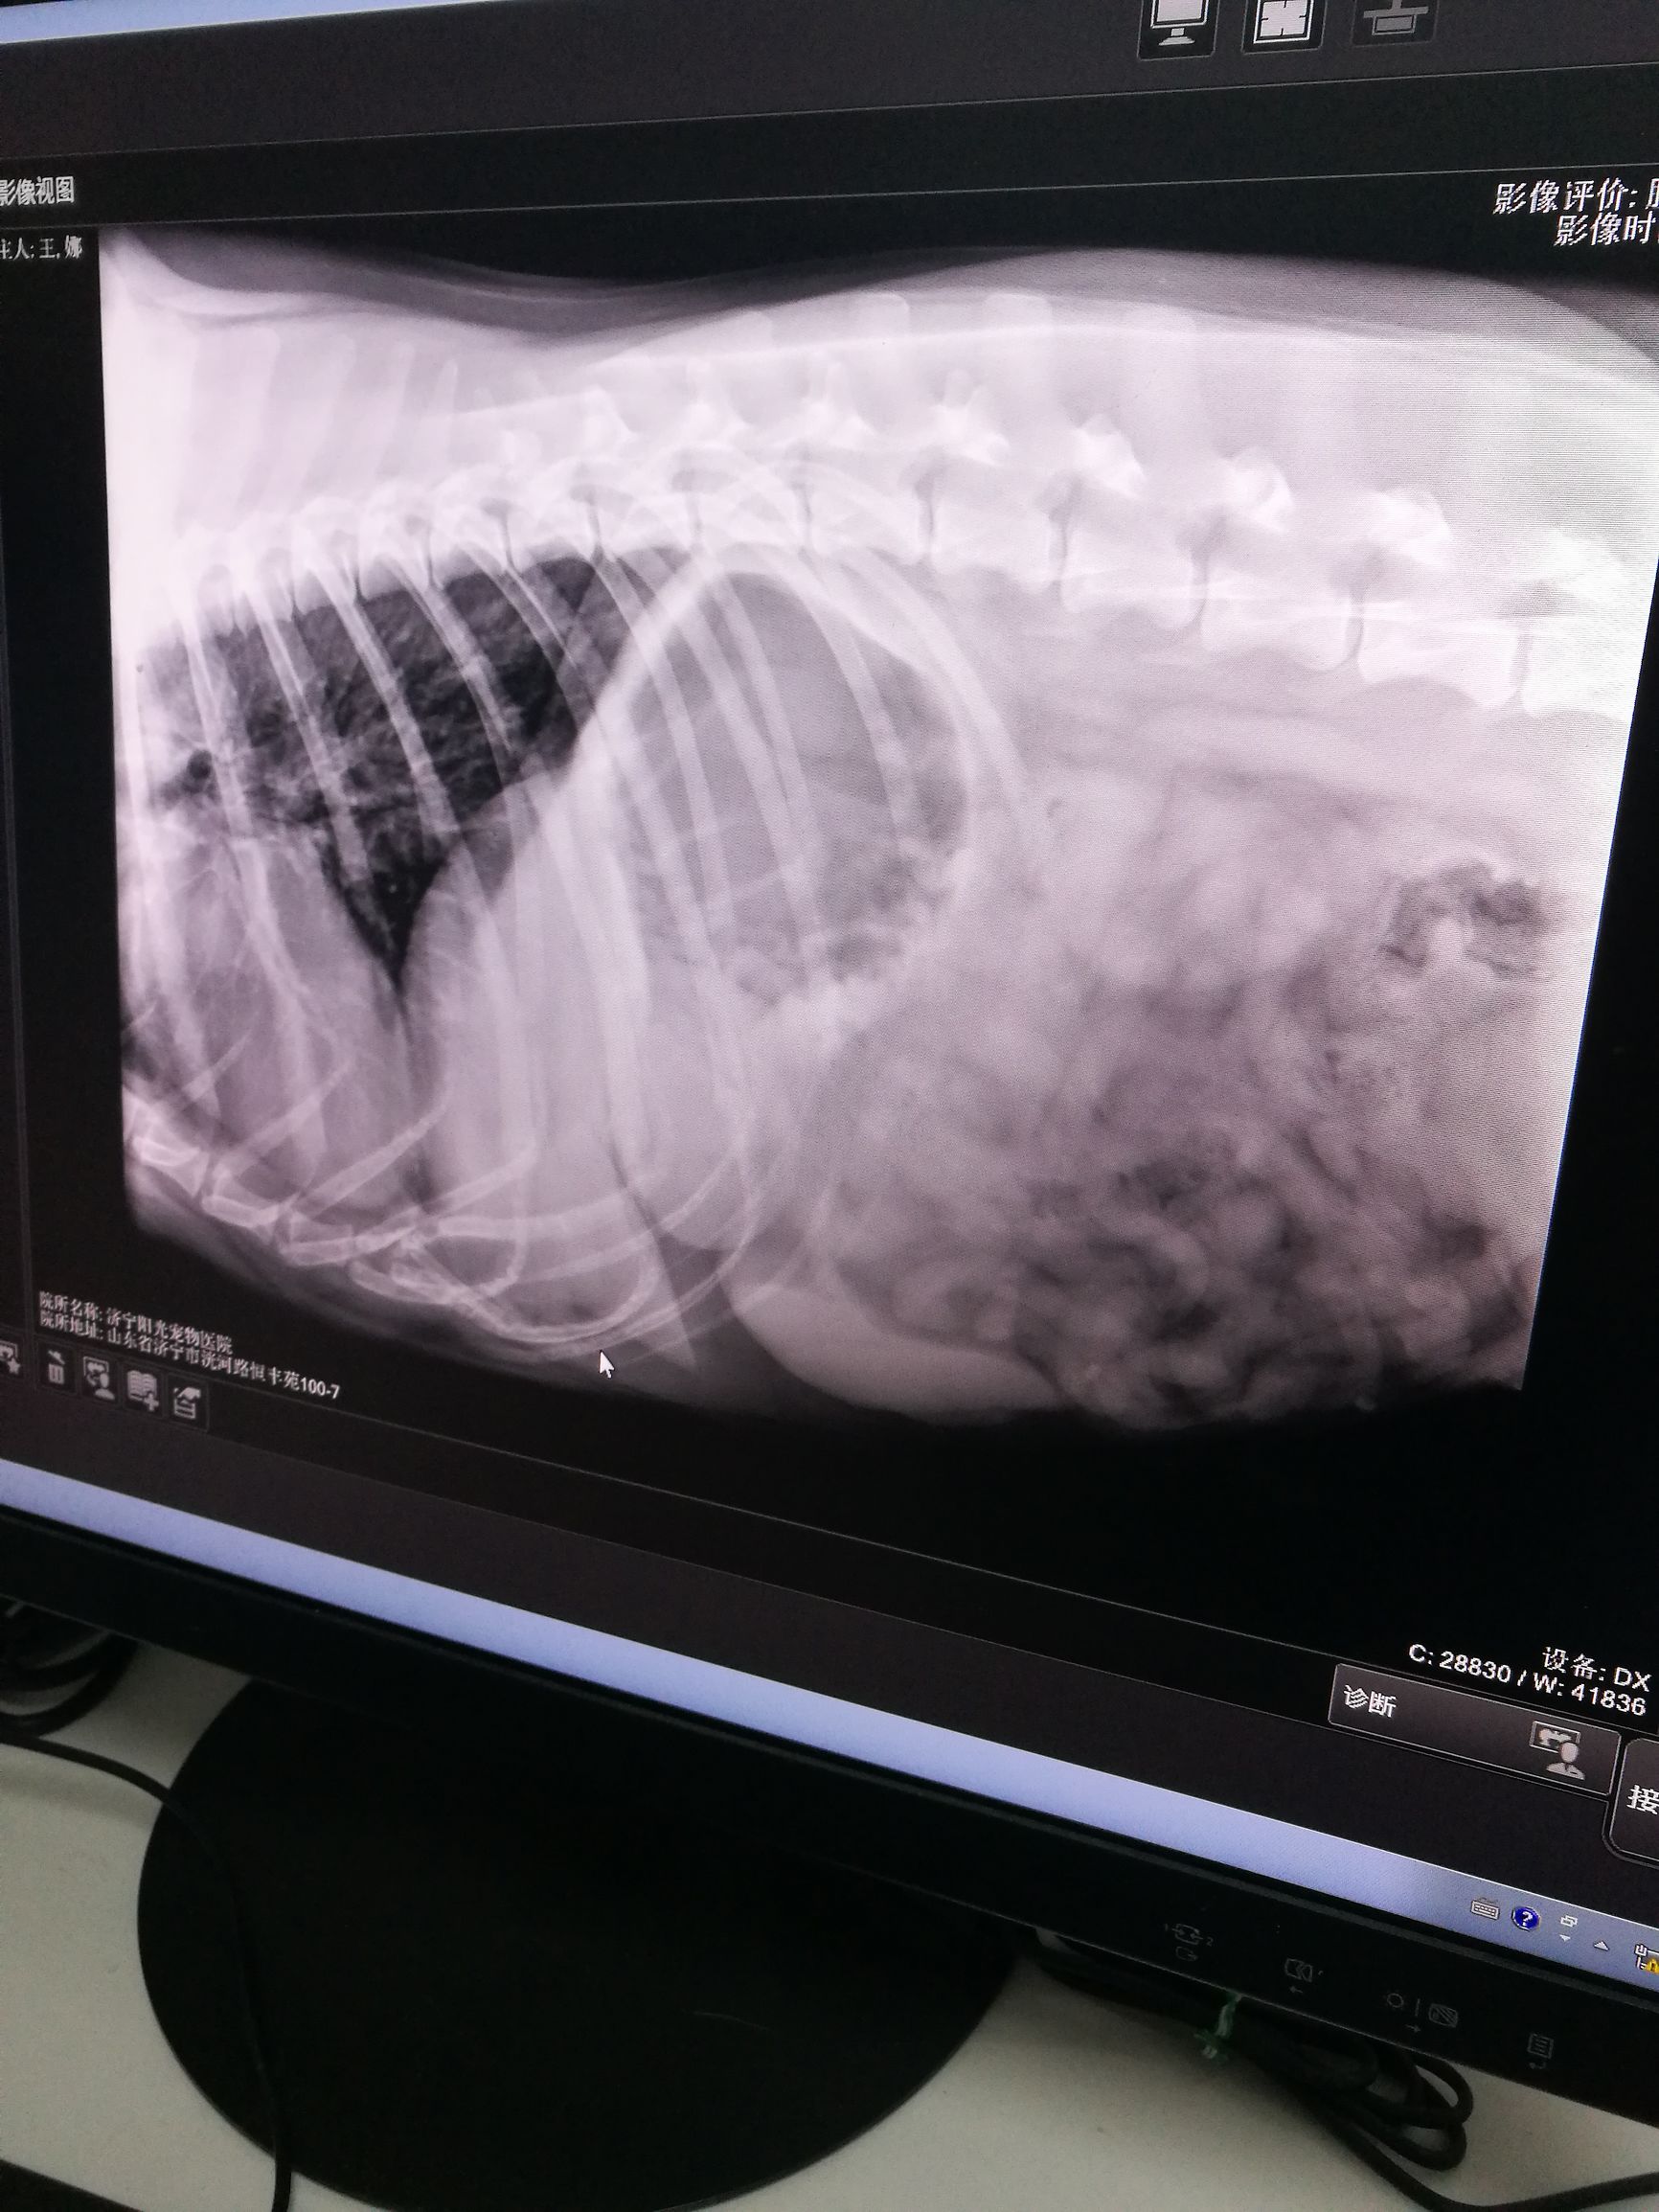

拉布拉多幼犬得传染病,拉布拉多犬得了狗瘟能活多久 ​看这张图我家狗子的影像图,我家狗狗三岁了,从来没这样过,这是原因是吃冻的生牛肉吃多了,医生给做了冠状病毒排查和胰腺炎排查等各项检查后拍了这个片子,真的太清晰,拍这个片子是为了看看是否胃扭转,因为我家狗子是一条中国登陆冠军犬,一个种公,身体壮的像一头牛呢,这几天呢正好出去配了两次种,我经验比较少点,出去配种前给它吃了饭,所以医生才会怀疑这个胃扭转,不过看了片子才真正放心,确定就是肠胃炎,打了两个小针,回家后就不吐了,是我害了我家狗狗,我不得不感叹如今宠物医院的医疗水平也是很先进很高啊!做生化全项,分离血清,各种试纸,由此可爱,狗子们的医疗以后和人的医院没啥两样了,虽然如此,但顺便提醒各位爱犬人士一定要引以为戒,别让狗子吃太多太凉了,千万不能吃未解冻的生牛肉啦!现在后悔的要命,我这个铲屎官这次可是记住了,害我家拉拉吐了一天,挨了四针,再夸一夸我家的狗狗囍多,